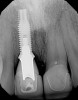

Fig 6. A radiograph taken at 10 years postoperatively demonstrates the predictable longevity of using PDGF for grafting procedures, as healthy bone support is observed.

Figure 6

Fig 11. The success and efficacy of this approach was confirmed radiographically at 8 years post-treatment, as demonstrated by the stable gingival margins, thickened biotype with a connective tissue graft, and stable bone levels observed at the first thread of the fixture.

Figure 11